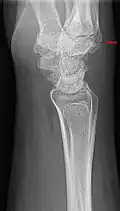

Carpal boss in plain X-Ray. Carpal boss in plain X-Ray.

The joint between the index metacarpal and the capitate is a fibrous non-mobile joint. Some people have a gene that leads to this growth. It looks like arthritis (bone spurs on each side of the joint) on X-ray. It looks like a ganglion on the hand, but more towards the fingertips.